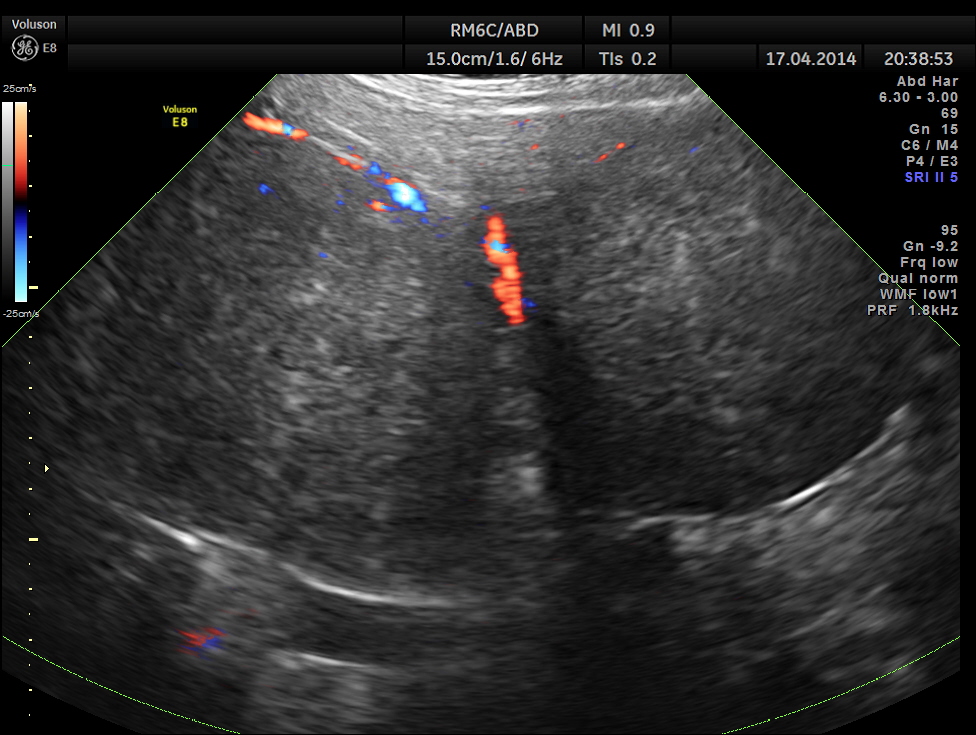

Thw two masses seen out of the uterus and mainly in the right upper quadrant are shown below.

The ultrasound gave us a few inconclusive findings . Uterus was massively enlarged ; a large fibroid was seen ; adenomyosis was seen ; endometrium was thickened ; two large mass lesions were seen in the right upper quadrant and right lumbar region . But it was difficult to ascertain the origin of these extra uterine masses .

Enlarged uterus with leiomyoma with mucinous and cystic degeneration and adenomyosis and two large sub serous fibroids arising from the fundal and right lateral aspect undergoing hyalinisation.

Reported as subserous and pedunculated . Looking at the pictures it appears as pedunculated